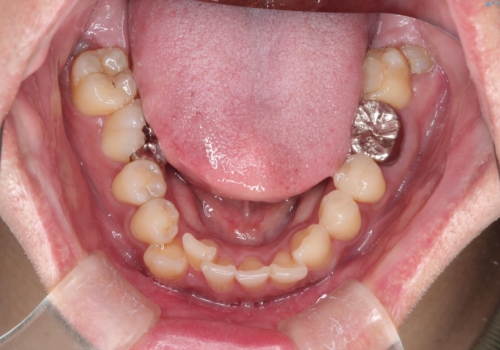

【ワイヤー矯正】八重歯と下の歯の凸凹を治したい

- 主訴:右上の八重歯と、下の歯の凸凹を治したい

上顎右側第一小臼歯と下顎右側第一小臼歯を抜歯しワイヤー矯正を行いました。

右側2級、左側1関係だったため、右側上下第一小臼歯を抜歯し、ワイヤー矯正を行いました。